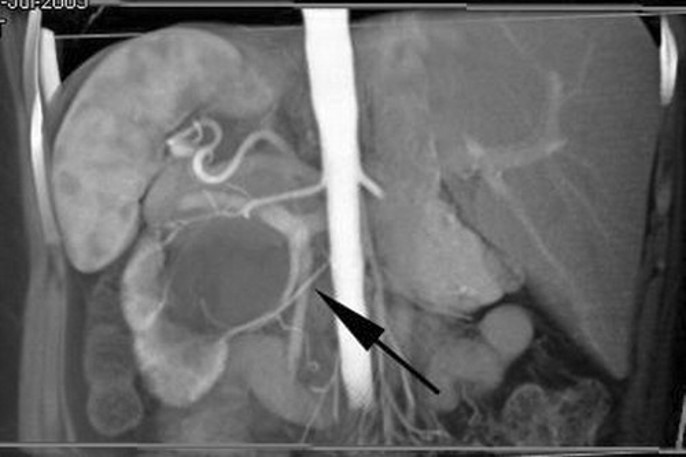

UPJ crossing vessel